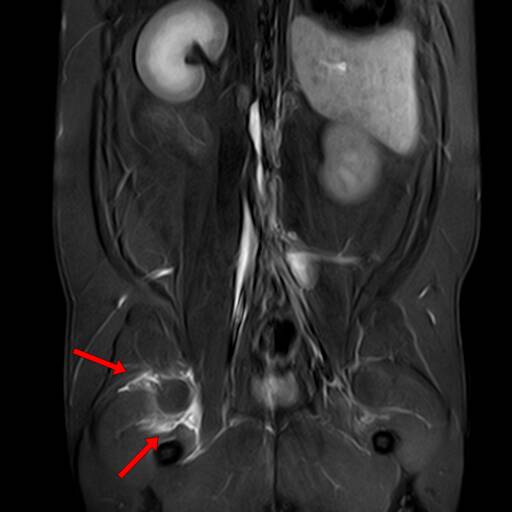

4.盆腔器官病变

适应症:犬前列腺疾病(前列腺炎、前列腺增生、前列腺癌,区分增生的良性腺体与恶性肿瘤);猫泌尿系统疾(膀胱肿瘤如移行细胞癌、膀胱壁增厚的性质判断);子宫疾病(子宫蓄脓、子宫肌瘤、子宫腺癌)等。

优势:MRI可显示前列腺包膜是否完整(癌性病变常突破包膜)、膀胱壁的分层结构(肿瘤导致的膀胱壁不规则增厚),为手术切除范围提供依据等。